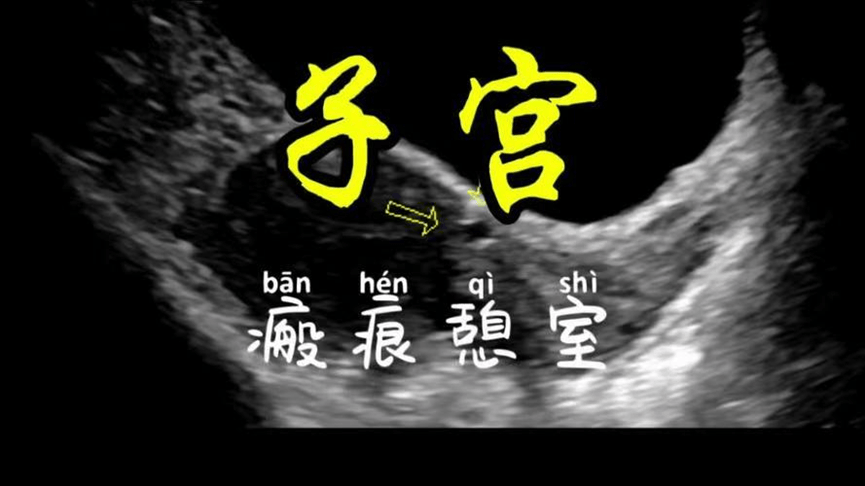

子宫卵巢b超

生完孩子月经淋漓8,9天,妇科b超查出子宫长了这个!